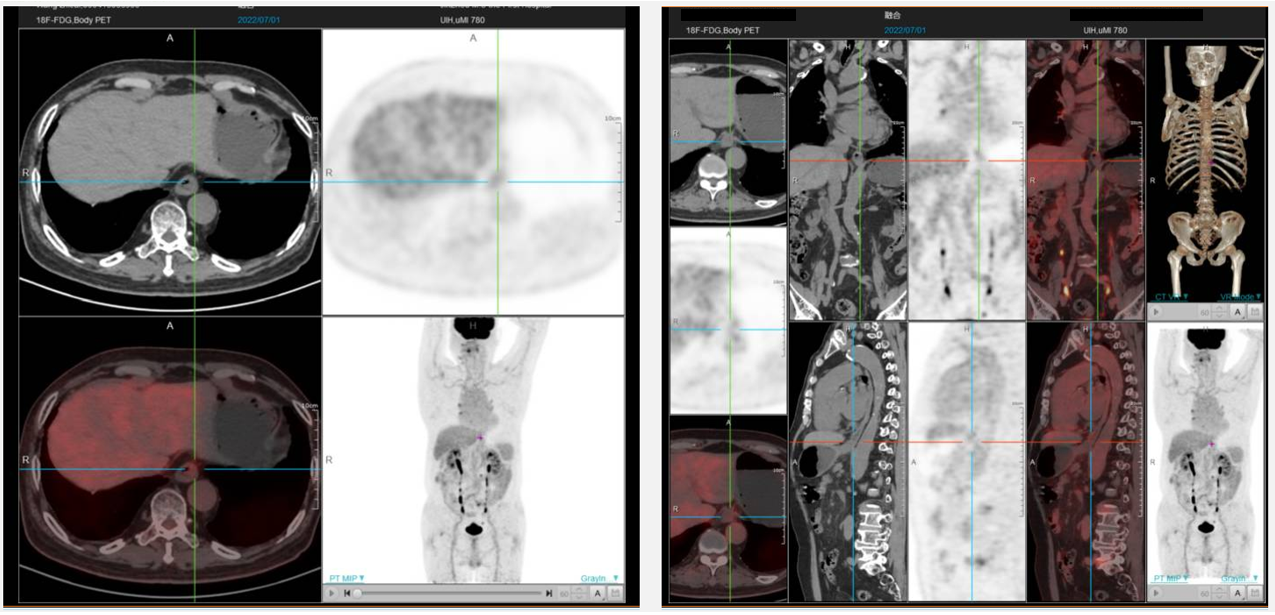

第3-5周期继续原方案治疗。第6周因手足反应较重,调整方案为替雷利珠单抗200mg+奥沙利铂200mg d1。其中于第4、6周期分别复查评估疗效。第4周期后CT显示食管下段进一步变薄。第6周期后复查,CT显示食管下段及贲门局部管壁治疗后改变,食管下段周围、胃小弯未见肿大淋巴结。PET/CT:食管MT治疗后病例:食管下段及局部贲门食管略厚,糖代谢正常,考虑治疗后改变;下段食管旁、胃小弯多发淋巴结影显示,伴轻度糖代谢,延迟显像轻度减低,考虑治疗后改变。复查胃镜:食管全程粘膜光滑,未见溃疡、糜烂;非萎缩性胃炎,十二指肠球炎。疗效评价CR。